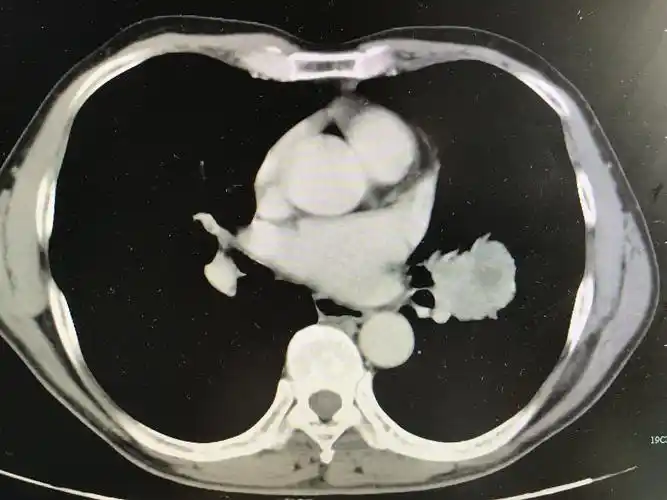

中央型肺癌ct

在ct上,肺癌按照发生部位可以分为以下3种类型: 1,中央型肺癌:指肿瘤

ct诊断中央型肺癌伴心脏转移一例